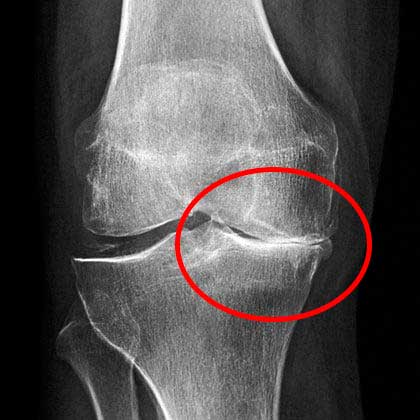

ตอนไปพบหมอครั้งแรก หมอใช้เวลานานมากในการดูภาพเอ็กซ์เรย์ แล้วบอกว่าให้ฉันเลิกทำงานหนักๆได้เลย และห้ามยกของหนักเกิน 2 กิโลกรัม

ภาพเอ็กซ์เรย์แสดงให้เห็นว่าเข่าของฉันมีปัญหาร้ายแรง

สภาพเข่าของฉันตอนนี้